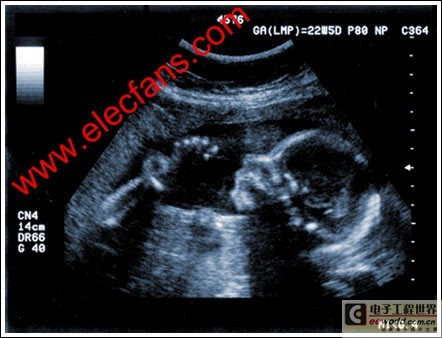

通过发射超声能量进入人体,接收并处理返回的反射信号,相控阵超声系统可以生成体内器官和结构的图像,映射血液流动和组织运动,同时提供高准确度的血流速度信息。传统设计中,构建这样的成像系统需要大量的高性能相控阵发射器和接收器,使得车载设备体积庞大且价格昂贵。近年来,随着集成工艺的进步,设计人员能够获得小尺寸、低成本而且高度便携的成像系统方案,并可达到接近大型成像设备的性能指标。而新的设计挑战依然存在,即在进一步提高方案集成度的同时提高系统性能和诊断能力。